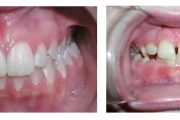

Lutipudelikaariese kahjustused

Lutipudelikaaries